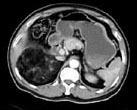

问题 男,59岁,右侧腰背酸痛,CT检查如图所示,应诊断为 ( )

选项 A、右腹膜后脂肪瘤 B、右肾血管平滑肌脂肪瘤 C、右肾上腺转移瘤 D、右肾上腺髓样脂肪瘤 E、右肾上腺腺瘤

答案 D